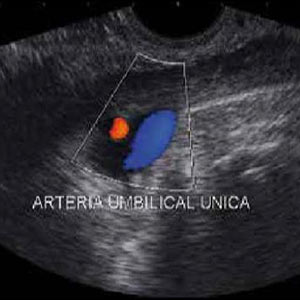

Ecocardiografía fetal: situación actual de diagnóstico en el Hospital Obrero N° 2, CNS Las cardiopatías congénitas constituyen las malformaciones fetales más frecuentes, con una incidencia mundial de 6 a 8 por mil nacidos vivos y 27 por mil nacidos muertos. |